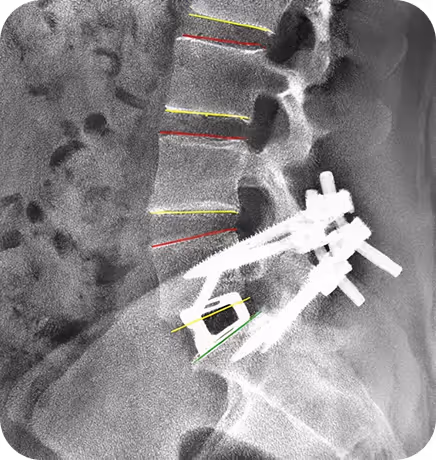

A Single Measurement for Scientifically Backed Spinal Alignment

Accurate pelvic incidence measurement is the starting point for selecting the appropriate PI-Rod curve and achieving optimal segmental alignment.

True lateral radiograph showing lumbosacral spine, pelvis, and superimposed femoral heads

Mark femoral head center and S1 endplate. If two femoral heads are visible and not superimposed, draw a line between their centers and mark the midpoint.

Draw line from femoral head center to midpoint of S1 endplate and draw a perpendicular line from the midpoint of the S1 endplate

Dorsal laser marks to designate target landing zone for pedicle screw tulip

Thick longitudinal line is the target zone